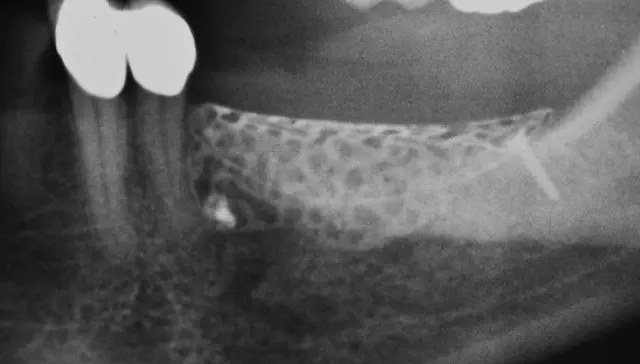

Abschließend wurde das beladene Gitter implantiert, mit einer individuell zugeschnittenen Kollagenmembran (Geistlich Bio-Gide) und mehreren PRF Matrizes abgedeckt und mit einer mehrschichtigen spannungsfreien Naht verschlossen (Abb. 21-24a). Abbildung 25b zeigt das postoperative Röntgenbild nach Gitterimplantation. Zum Schutz des Aufbaus wurde eine Verbandplatte eingesetzt (Abb. 25 a und b) und die Patientin ausführlich über das postoperative Verhalten aufgeklärt. Acht Tage postoperativ zeigte sich die Wunde in regelrechter, zeitlich entsprechender Heilung, woraufhin eine Teilnahtentfernung mit Belassen der tiefen Stabilisierungsnähte erfolgte (Abb. 26).

Praxis Dr. Dr. Tröltzsch